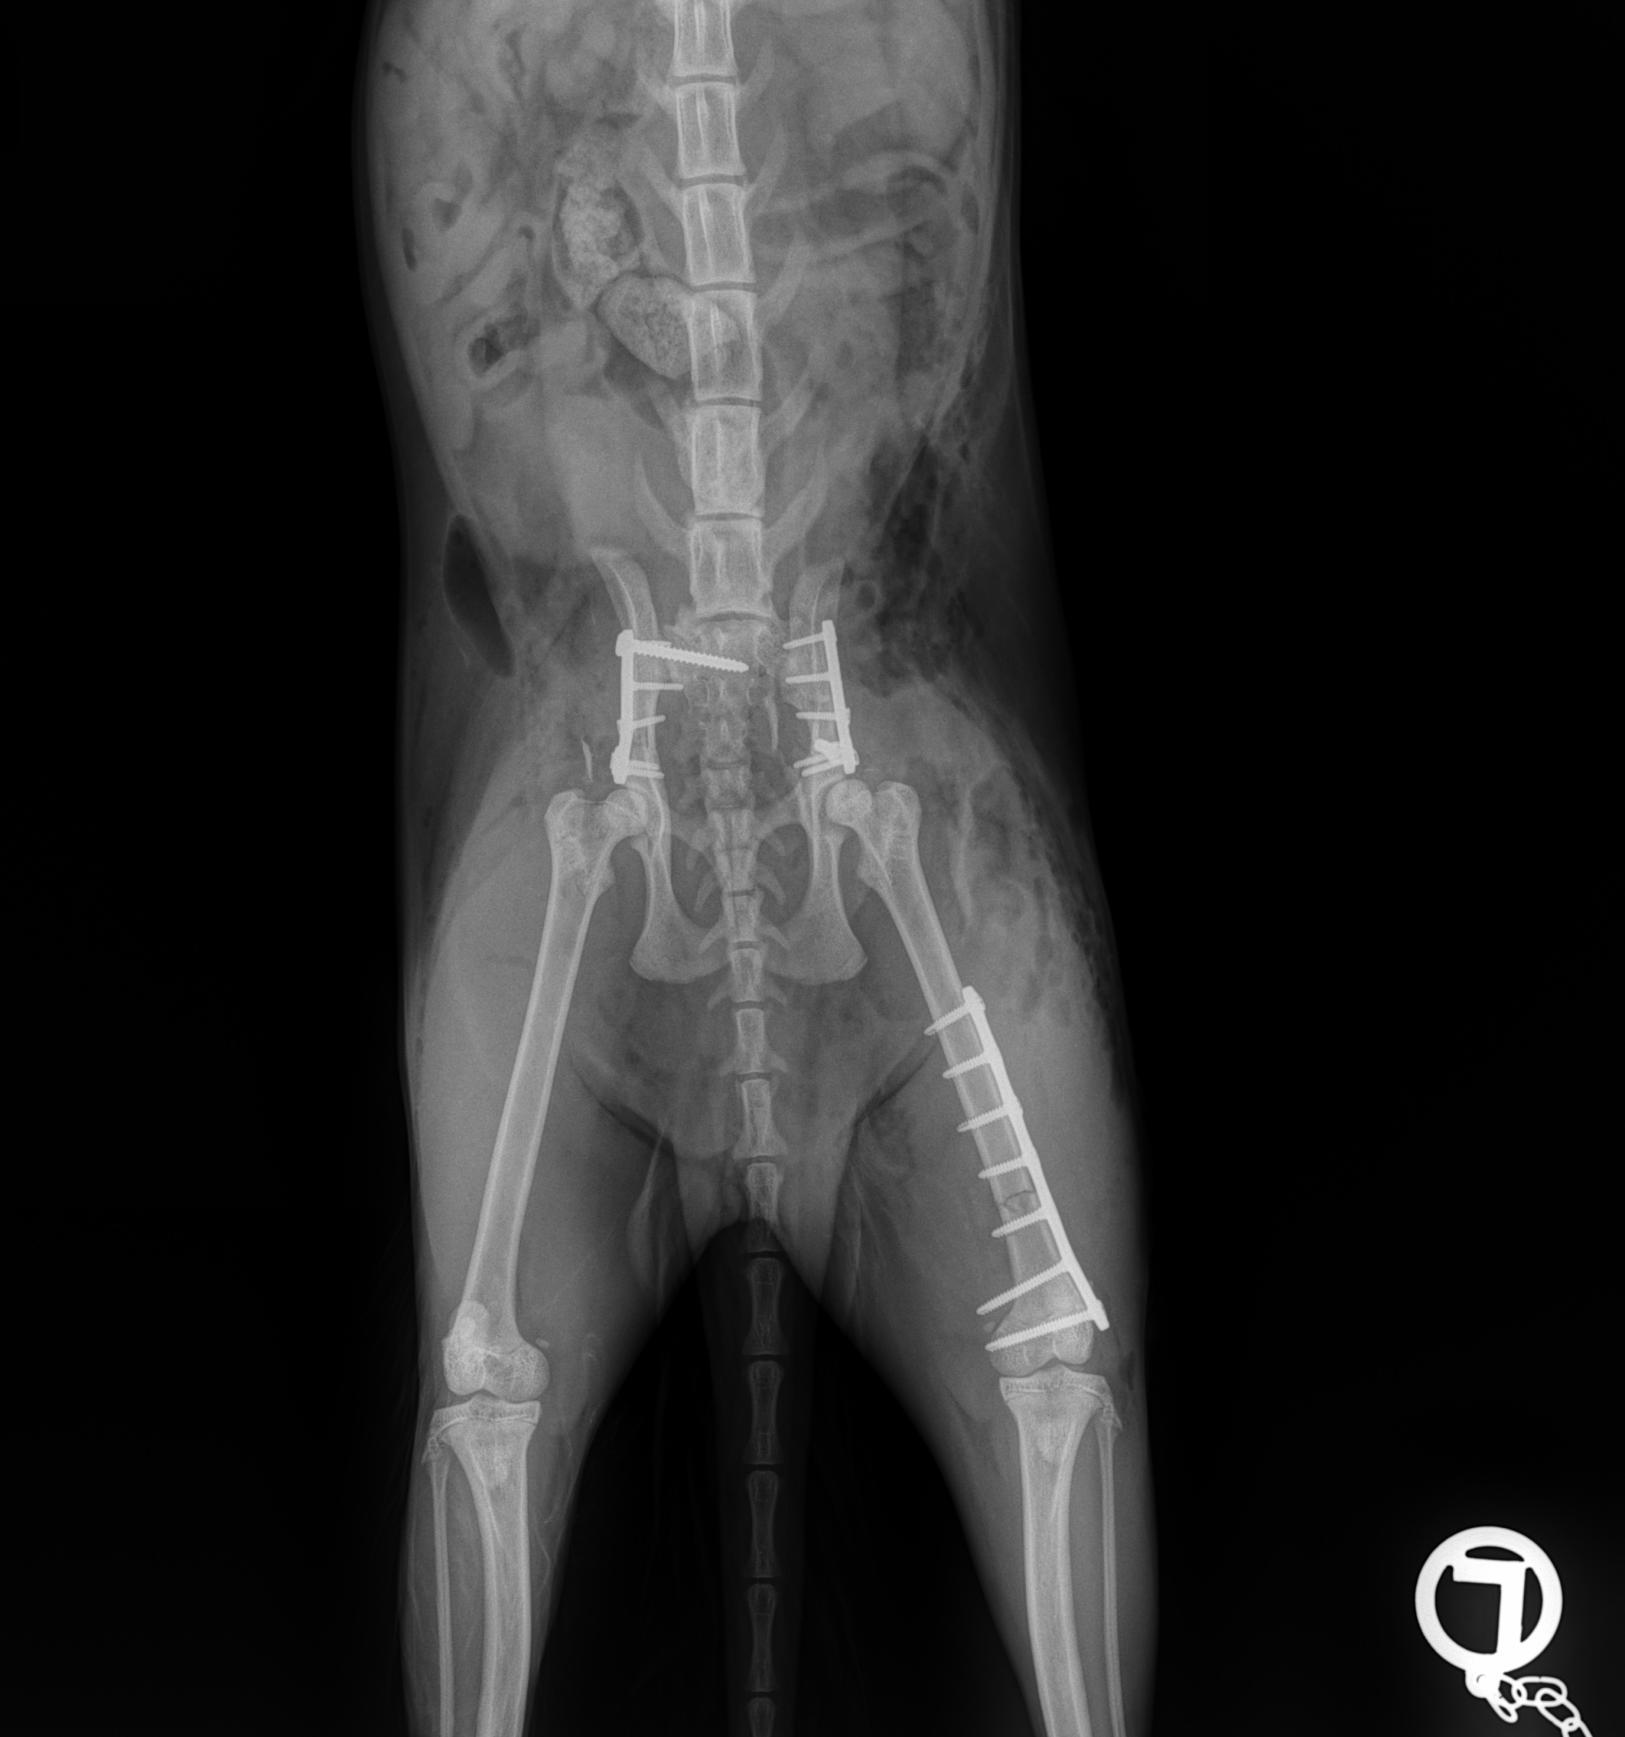

Case Overview In November 2025, Skeeter, a 14-week-old Doodle puppy weighing ...